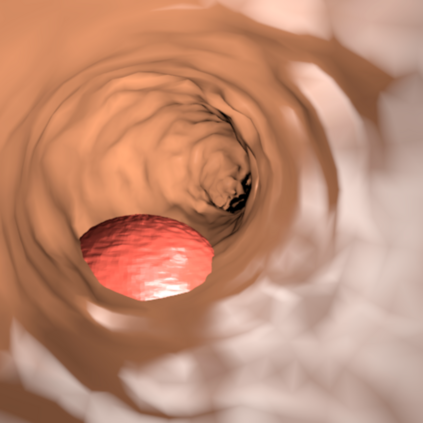

Deep learning has shown excellent performance in analysing medical images. However, datasets are difficult to obtain due privacy issues, standardization problems, and lack of annotations. We address these problems by producing realistic synthetic images using a combination of 3D technologies and generative adversarial networks. We use zero annotations from medical professionals in our pipeline. Our fully unsupervised method achieves promising results on five real polyp segmentation datasets. As a part of this study we release Synth-Colon, an entirely synthetic dataset that includes 20000 realistic colon images and additional details about depth and 3D geometry: https://enric1994.github.io/synth-colon